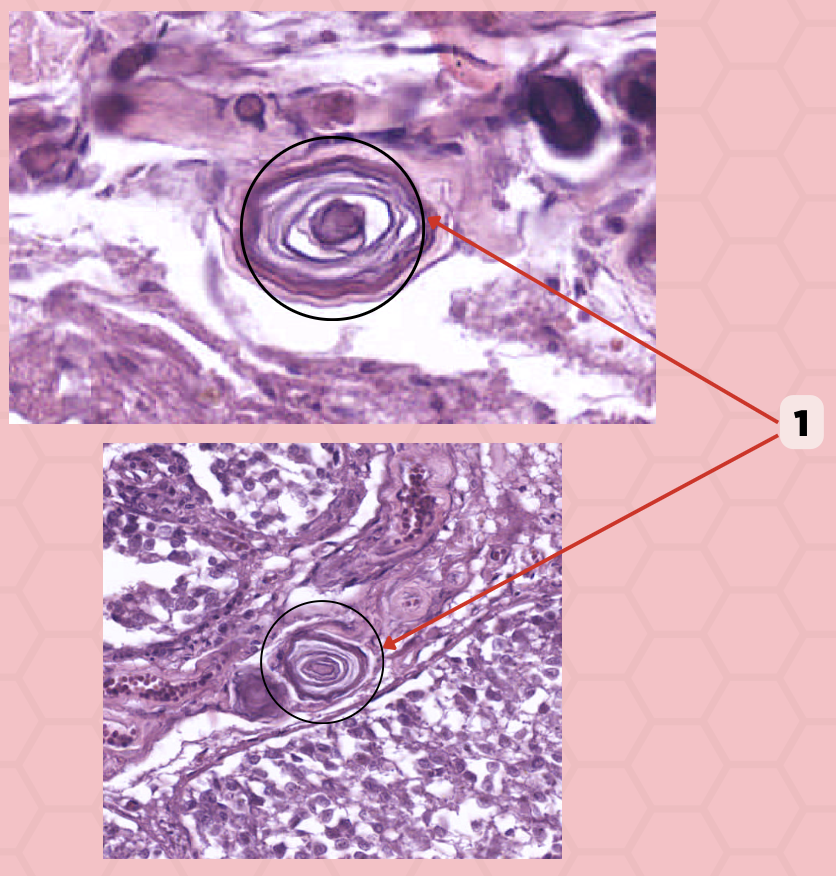

True

True or False: These (#1) are extracellular/calcified bodies that increase with age.

Corpora Arenacea

Identify the structure labeled as 1.